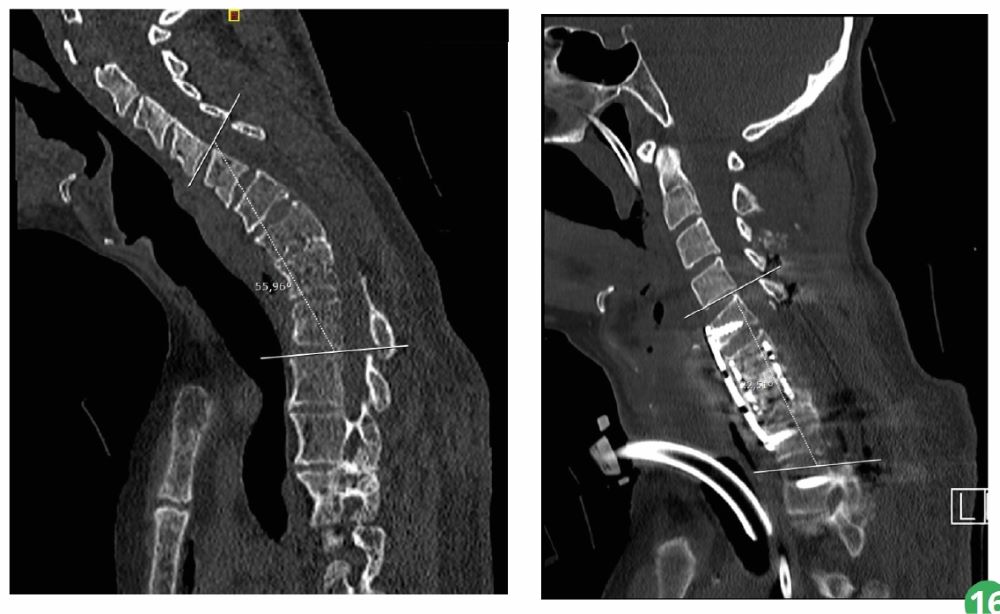

Dr. Jorge Herreria and Dr. Fabián Romero, from neurosurgery service both Parc Taulí, have csuccessfully corrected a cervical curvature of 56º using 3D technology to a 40-year-old patient who had previously been operated on for a shot to the neck, which had produced a spinal cord injury.

The patient suffered from unbearable pain in the cervical area. After carrying out a study, an abnormal curvature of the cervical vertebrae was detected due to a fracture of the C6 and C7 vertebrae, which had caused a kyphotic deformity, a curvature of the cervical vertebrae.

After presenting and studying the case with the team of neurosurgeons, due to its complexity because the cervical vertebrae are smaller and the patient had already been operated on previously, it was decided to perform a surgical operation to correct the cervical deformity, with an inverted curve of 56º, and fix this position on the cervical spine.

The operation was a success, it was possible to correct more than 33º of the previous kyphosis by fixing the patient's neck in a practically normal position, of 20º.